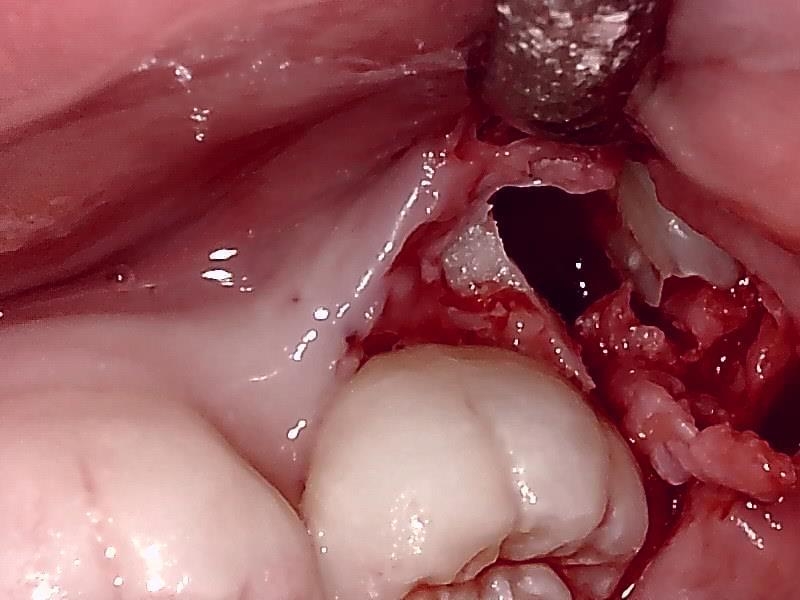

分割して隙間から抜去する。

歯根を隙間から抜去していく